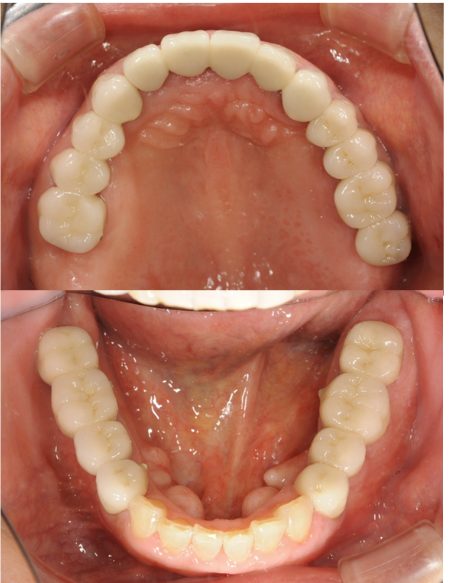

| 主訴 | 全顎治療希望、歯が無いので噛みずらい。定年で時間の余裕出来たので、インプラントで治療して欲しい。 |

| 治療内容 | プラークコントロール不良なため歯周治療を行い、残存歯を極力温存し、欠損部インプラントを施し咬合再構成を行う。 プロビジョナルレストレーションによる咬合関係を模索した後、全顎にわたりセラミックによる補綴治療、その後メインテナンスに移行 |

| 治療費 | 6,470,000円(税込)(インプラントすべて含む) |

| 治療期間 | 1年6ヶ月 |

| 治療回数 | 72回 |

| 想定されたリスク | 食いしばり(パラファンクション)によるセラミックの破折、歯の破折 |